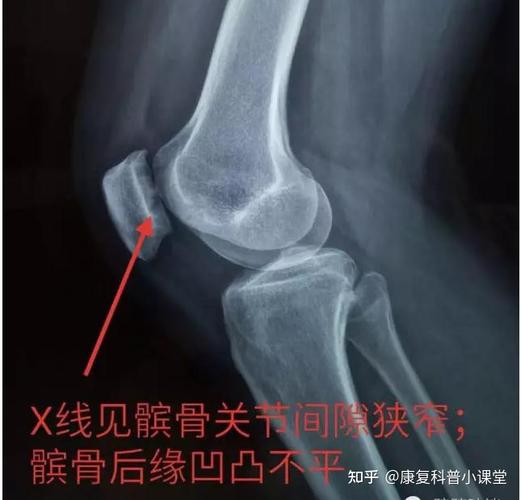

英文全称: patello femoral pain syndrome, 又称为:髌骨软化症

髌骨软化症片子图片

髌骨软化症图片示意图

髌骨软化症mri图解